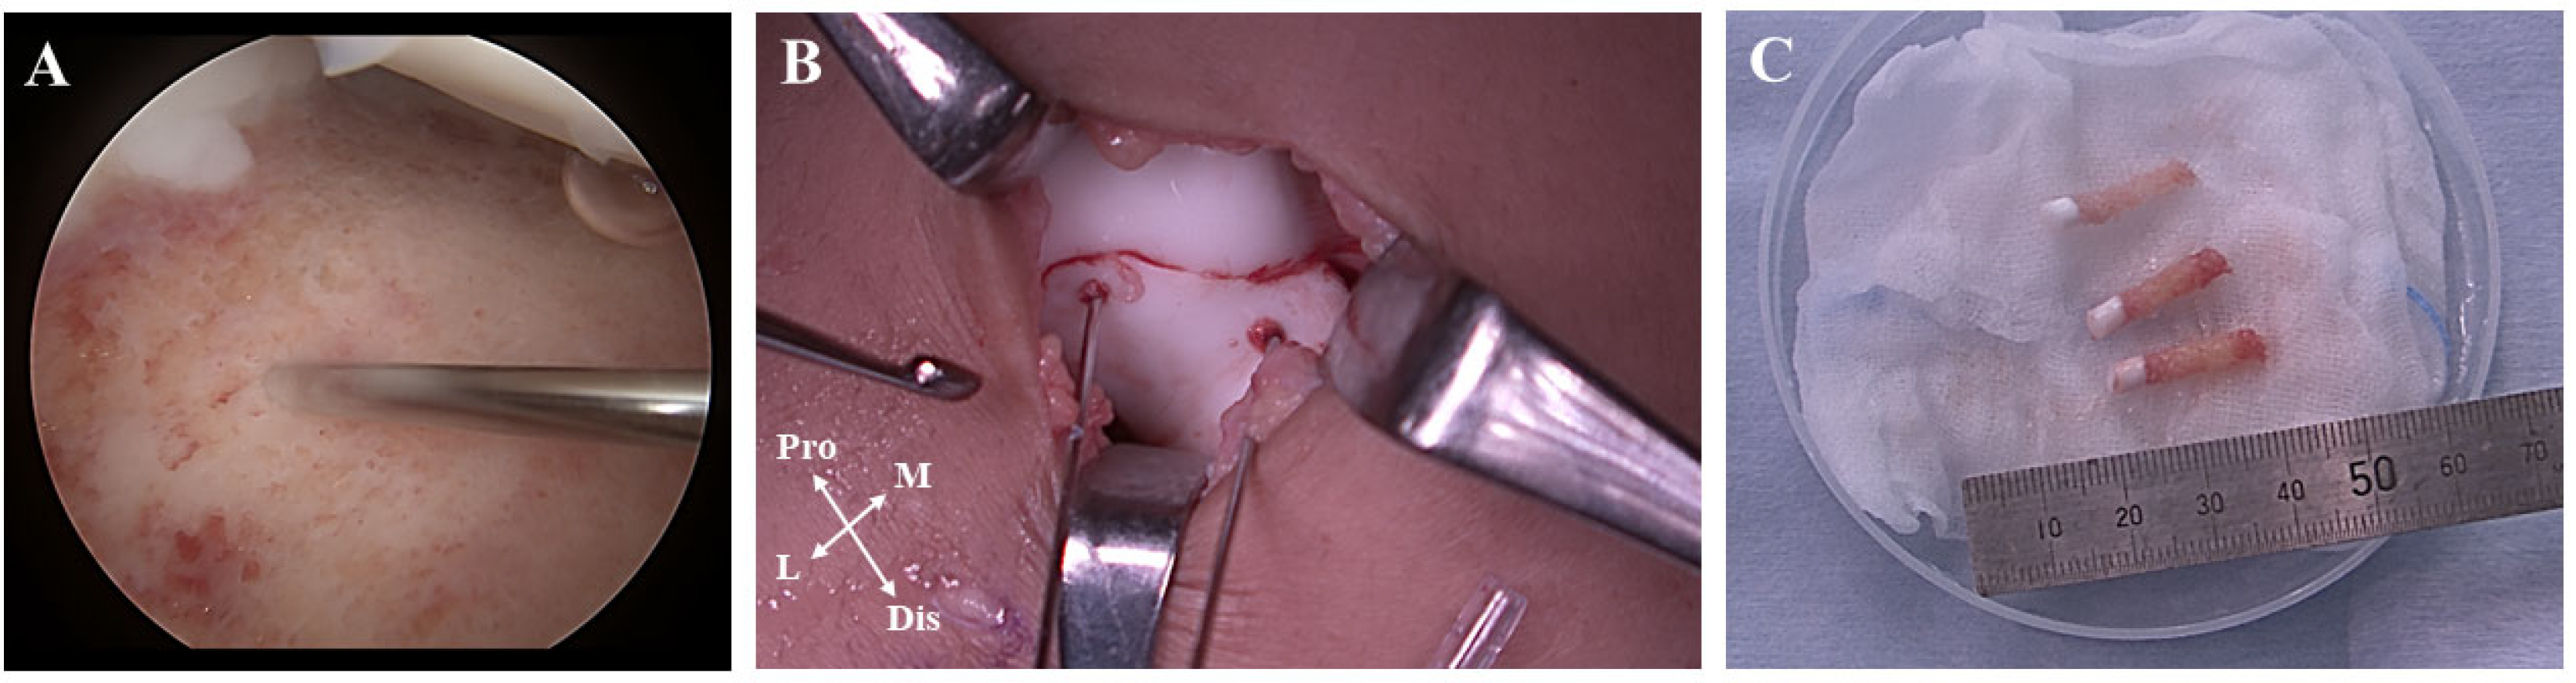

2. Case Presentation